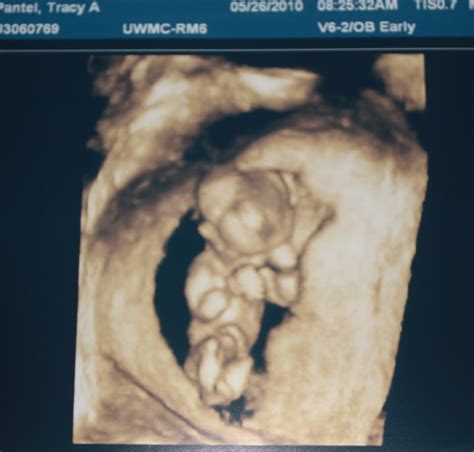

Pregnancy is an exciting journey filled with milestones, and one of the most anticipated is the 12 week ultrasound. This crucial scan provides valuable insights into the development of the fetus and the overall health of the pregnancy. Understanding what to expect during this ultrasound can help alleviate anxiety and prepare expectant parents for the experience.

A 12 week ultrasound, also known as the nuchal translucency scan, is typically performed between 10 weeks and 13 weeks and 6 days of pregnancy. This scan is essential for several reasons, including assessing the baby’s development, checking for any potential abnormalities, and measuring the nuchal translucency, which is the fluid-filled space at the back of the baby’s neck. This measurement is crucial for screening for chromosomal abnormalities such as Down syndrome.

The 12 week ultrasound is usually performed transabdominally, meaning the ultrasound probe is moved over the abdomen. In some cases, a transvaginal ultrasound may be used for better visualization, especially if the baby is positioned deeply in the pelvis.

During the procedure, the technician will apply a gel to the abdomen to enhance the transmission of sound waves. The probe will then be moved over the abdomen to capture images of the fetus. The entire process typically takes about 20-30 minutes.

During the 12 week ultrasound, several key measurements and assessments are made:

• Crown-Rump Length (CRL): This measurement from the top of the baby’s head to the bottom of the spine helps determine the gestational age and due date.

• Nuchal Translucency (NT): The thickness of the fluid-filled space at the back of the baby’s neck is measured. This measurement, along with maternal age and blood tests, helps screen for chromosomal abnormalities.

• Heartbeat: The baby’s heartbeat is checked to ensure it is within the normal range.

• Anatomy: The technician will look for the presence of the nasal bone, which is an important marker for Down syndrome. They will also check for the presence of both arms, legs, and the stomach bubble.